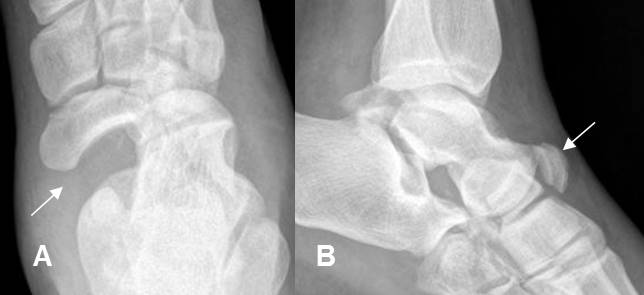

Fig 183. Fractura de Chopart.

A: Rx AP y B: Rx lateral. Luxo fractura de la articulación taloescafoidea.

Fig 196. Fractura de Lisfranc.

A: Rx AP. Pérdida en la nitidez en las 2º y 3º articulaciones tarsometatarsianas, por fracturas no desplazadas en el plano AP.

B: TAC reconstrucción coronal. Fracturas conminutas en la cuña media y lateral, las cuales están desplazadas posteriormente.